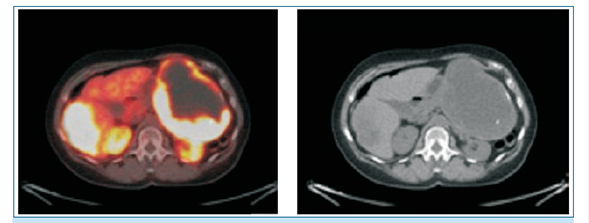

Medicina nuclear: PET 68 Ga-DOTATATE: expresión de receptores de somatostati- na en cola y cuerpo de páncreas. Secundarismo hepático múltiple (figura 1).

Figura 1: PET 68Ga-DOTATATE previa al tratamiento con lutecio 177-DOTATATE.